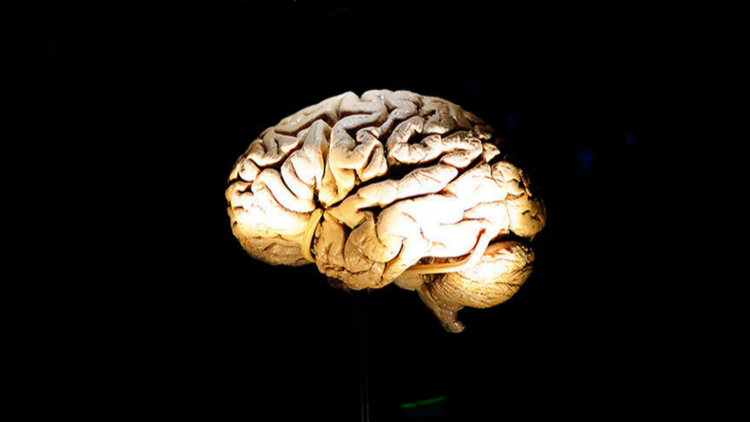

اكتشاف ثوري.. المخ يستطيع تخزين ذكريات أكثر بـ10 أضعاف مما كان يعتقد سابقا

وجدت دراسة ثورية جديدة أن الدماغ البشري يمكنه أن يخزن ذكريات أكثر بـ 10 أضعاف مما كان يُعتقد سابقا، ومفتاح هذه القدرة المذهلة يكمن في نقاط الاشتباك العصبي والوصلات العصبية.

وقد توصل العلماء إلى هذه النتيجة الجديدة بفضل مواصلة البحوث في نقاط الاشتباك العصبي والوصلات العصبية المسئولة عن تخزين الذكريات في المخ.

ووجد الباحثون من معهد سالك Salk Institute أن كل نقطة اشتباك عصبي يمكن أن تخزن حوالي 4.7 بت من المعلومات، وهذا يعني أن الدماغ البشري لديه قدرة على تخزين واحد بيتابايت من المعلومات، أي ألف تريليون بايت، وهذا يعادل حوالي 20 مليون خزانة من 4 أدراج لحفظ الملفات مليئة بالبيانات.

وجاء اكتشاف هذه القدرات المذهلة للدماغ البشري بينما كان العلماء يقومون بإعادة بناء نموذج ثلاثي الأبعاد من أنسجة فرس البحر لاستخدامه كبديل لخلايا الدماغ.

وعند اكتشاف العلماء هذا الأمر، لم يستطيعوا تخيله في البداية، ولكن لفهم حقائقه كان لابد لهم من فهم الآلية العلمية لعملية تكوين الذكريات في المخ.

ويقول العلماء إن الذكريات والأفكار هي نتائج أنماط النشاط الكهربائي والكيميائي في الدماغ، ويحدث الجزء الحيوي من هذا النشاط عندما تتقاطع فروع الخلايا العصبية في بعض مناطق المخ، والمعروفة باسم نقاط الاشتباك العصبي.

وذهب فريق العلماء في الدراسة الجديدة إلى استنتاج مفاده أنه يمكن أن يوجد في المُخ نحو 26 فئة مختلفة الأحجام من نقاط الاشتباك العصبي، بينما كان يعتقد في السابق أن عددها أقل من ذلك بكثير، كما توصل الفريق أيضا إلى أن الأحداث التي تمر على الدماغ تتسبب في تغيير حجم نقاط الاشتباك العصبي، فهي "تضبط نفسها وفقا للإشارات التي تتلقاها".

هذا ويمكن أن تساعد هذه الدراسة علماء الكمبيوتر على بناء أجهزة كمبيوتر موفرة للطاقة، وخاصة تلك التي تستخدم مهام "التعلم العميق" والشبكات العصبية الاصطناعية، وهي التقنيات القادرة على التعلم والتحليل المتطورين، مثل القدرة على الكلام والتعرف على الوجوه والترجمة.